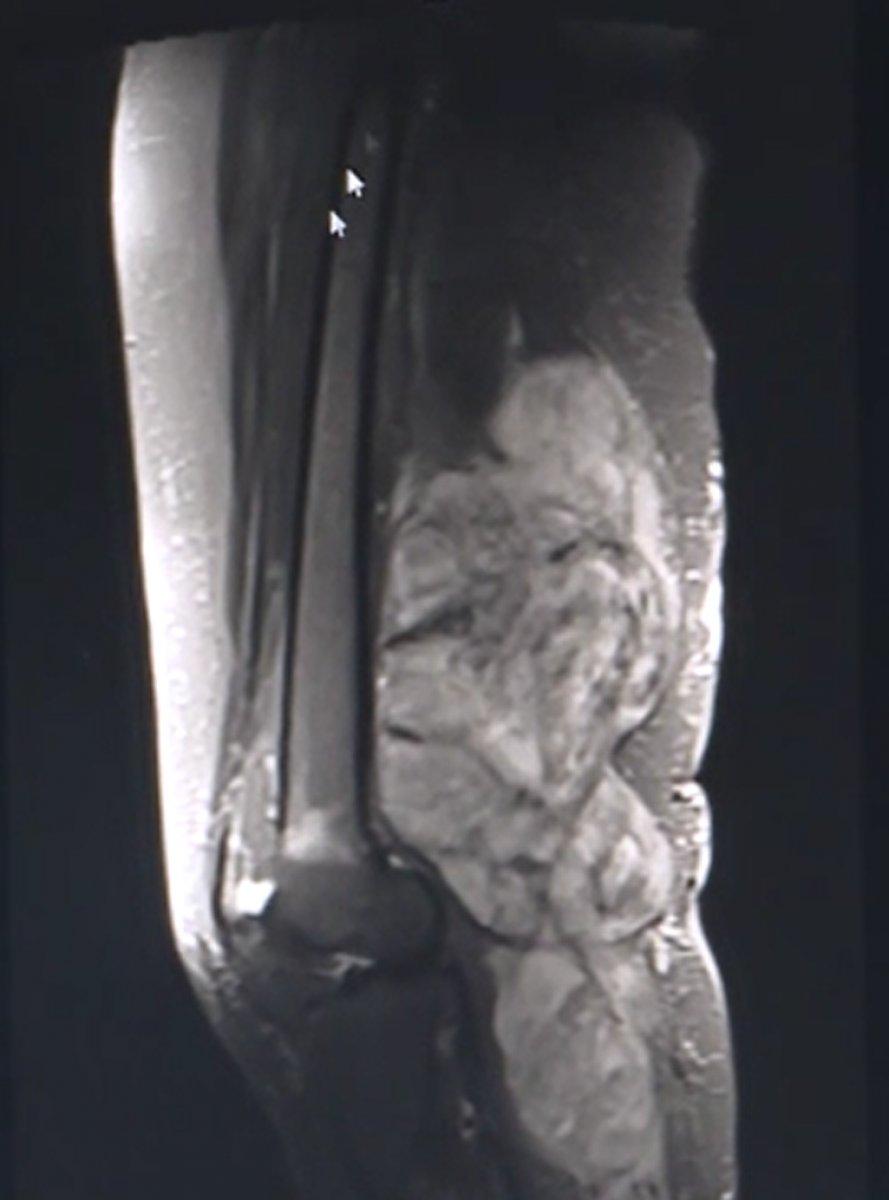

Ortopedi ve Travmatoloji Ana Bilim Dalı'nda görevli Doç. Dr. Kutsi Tuncer'e muayene olan Çelik'in yapılan detaylı görüntüleme ve tetkiklerinde, bacağının büyük kısmını kötü huylu tümör sardığı tespit edildi.

"Hasta için görüntüleme yöntemlerine başvurduğumuzda, uyluğundan başlayıp dizinin arka kısmından baldıra kadar devam eden 35 santimetre uzunluğundaki 15 santimetre genişliğindeki yumuşak doku kitlesini fark ettik. Sonra o bölgeden aldığımız patolojik örneğin sonucu, yağ dokusundan kaynaklı kötü huylu yumuşak doku tümörü olarak geldi."